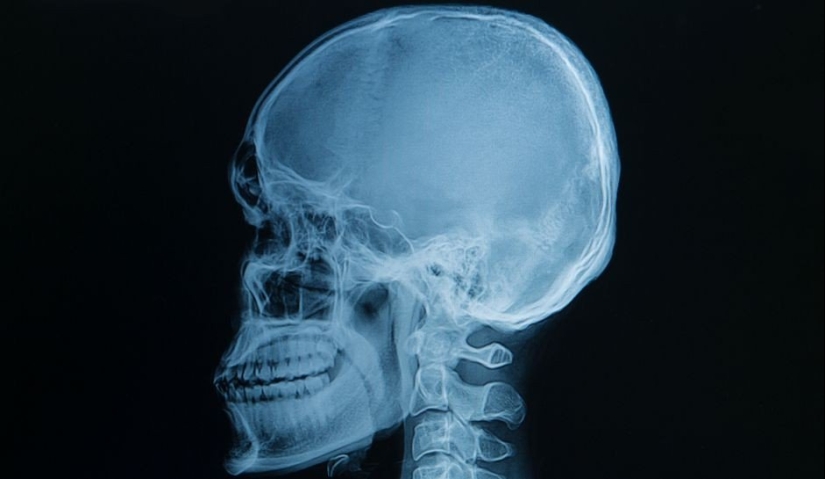

Una imagen que hizo temblar a decenas de personas. Así es como se ven los dientes humanos dentro de la mandíbula.